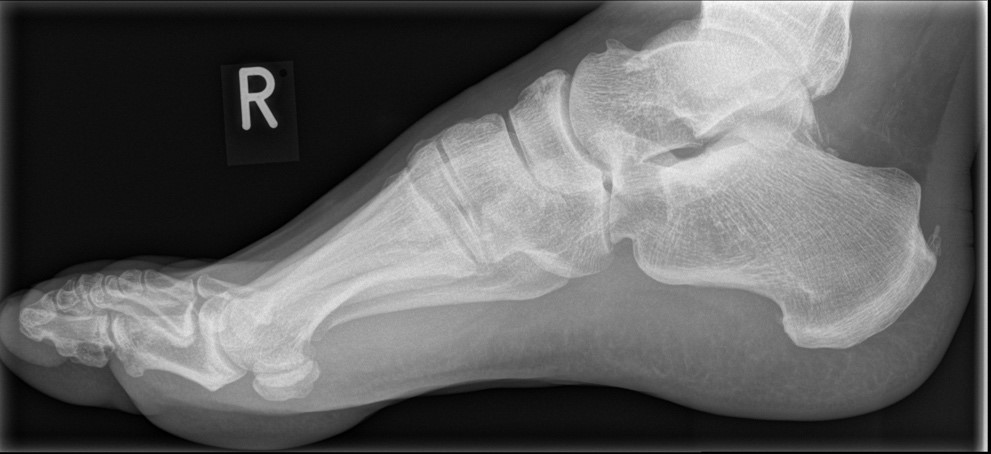

Abb. 9a–d: chron. Plantarfasziitis mit plantarem Fersensporn und Irritation Baxternerv plantar lateral

Kasuistik: 28-jähriger Patient, Profisportler.

Abb. 9a: Plantarer Fersensporn und Plantarfasziitis im MRT prä-op.

Abb. 9b: Plantarer Fersensporn im CT prä-op.

Abb. 9c: Lateraler Zugangsweg bei atypisch weit nach plantar lateral liegendem Sporn.

Abb. 9d: Röntgenkontrolle nach Minioffenem Plantarfaszienrelease und Abtragung Fersensporn mit Neurolyse.

Zum Lesen der Bildbeschreibung und zur Vollansicht bitte die Bilder anklicken. Bilder: Manfred Thomas.